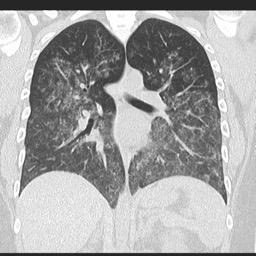

o   Vysokorozlišovací CT (HRCT): Ukazuje difúzní skleněné opacity a ukládání hemosiderinu

o   HRCT: Ukazuje intersticiální plicní onemocnění a skleněné opacity

o   HRCT: difúzní sklovité opacity a alveolární konsolidace.

Difúzní alveolární krvácení v důsledku vaskulitidy

Zdroj: radiopaedia.org